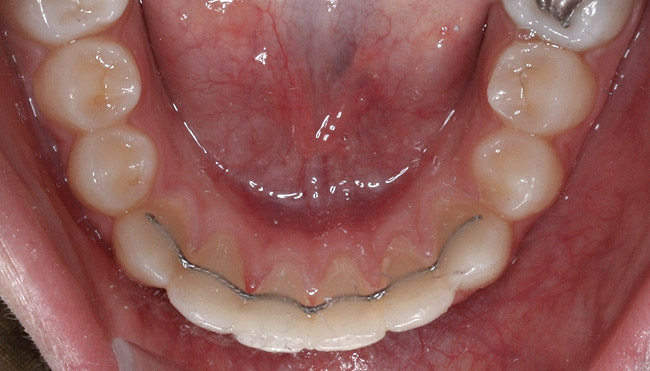

Fig 16. Occlusal view of patient shows the difference in angulation between the affected and the adjacent incisors.

Figure 16